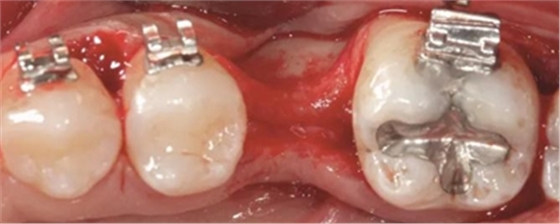

圖5c. 翻全厚瓣后,看到嚴(yán)重的牙槽嵴吸收

圖5d. 在骨移植受植處、第二磨牙和第三磨牙牙根之間以及第三磨牙遠(yuǎn)中進(jìn)行去皮質(zhì)術(shù)